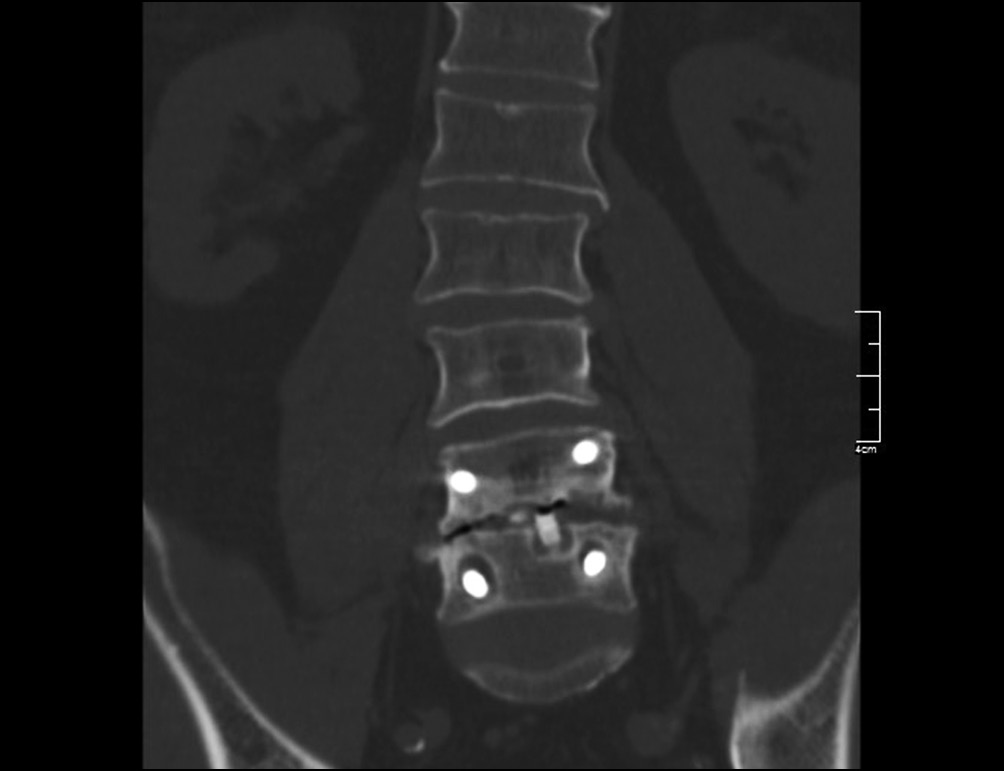

Средние сроки диагностирования резорбции костной ткани вокруг винтов по данным КТ поясничного отдела позвоночника составили 10,1 мес. [4, 2; 20, 6] (от 18 дней до 4 лет) (рис. 1).

Рис. 1. Резорбция вокруг винтов в теле позвонка и в ножках дужки на сроке 11 мес. после первичного хирургического вмешательства